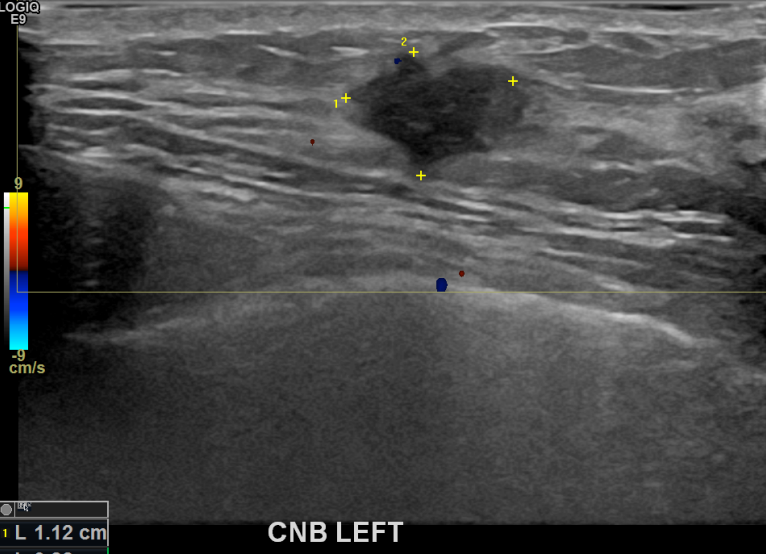

상기환자 만져지는 멍울있어 조직검사 권유받고 내원하신 40대 여성분으로 좌측유방멍울 조직검사시행후 유방암 진단되었습니다.